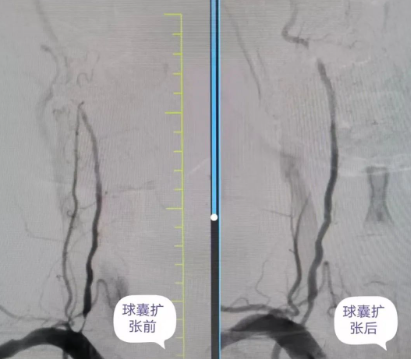

術(shù)中,丁金明主任、朱洪波副主任帶領(lǐng)團隊,通過導管精準地將球囊送至狹窄的椎動脈段,在確認球囊位置準確無誤后,仔細地進行擴張,直至狹窄的血管恢復(fù)到接近正常直徑。整個手術(shù)過程在專業(yè)團隊的精心操作下,僅30分鐘便順利完成。